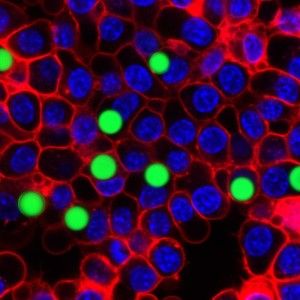

The extreme precision of that output is one thing that makes the tiny lasers so promising. The soft droplet versions shift shape ever so lightly when under stress, and that deformation makes a visible change in the laser's emission spectrum, so that even minute changes in the cell can be recorded in fine detail. Similarly the team can produce lasers of slightly different wavelengths by changing the size of the hard beads—enabling them to uniquely color code an individual cell and potentially label thousands of different cells within a single tissue, according to the research published this week in Nature Photonics.

“The spectral peaks of the laser are very sensitive to the local environment, and you can design the laser so it senses certain biomarkers and changes the output wavelength when they change even in tiny shifts,” Yun notes. This means the laser can deliver highly detailed information about cell surfaces, hormones and even the cell's protein production. The lasers could also be used to tag individual cells and thus paint a far more detailed picture of how a larger object, like a tumor, changes over time.

“You could see exactly where the individual cells go in the body, which ones metastasize earlier than others, and study the growth of shrinkage of a tumor at the individual cell level,” Yun says.

Perhaps most promising of all is the potential to not only monitor aspects of human health but to actively improve them, he adds: “These laser-equipped cells could also potentially be loaded with light-activated drugs and delivered to a specific location, where they might be used to kill a tumor, for example.”